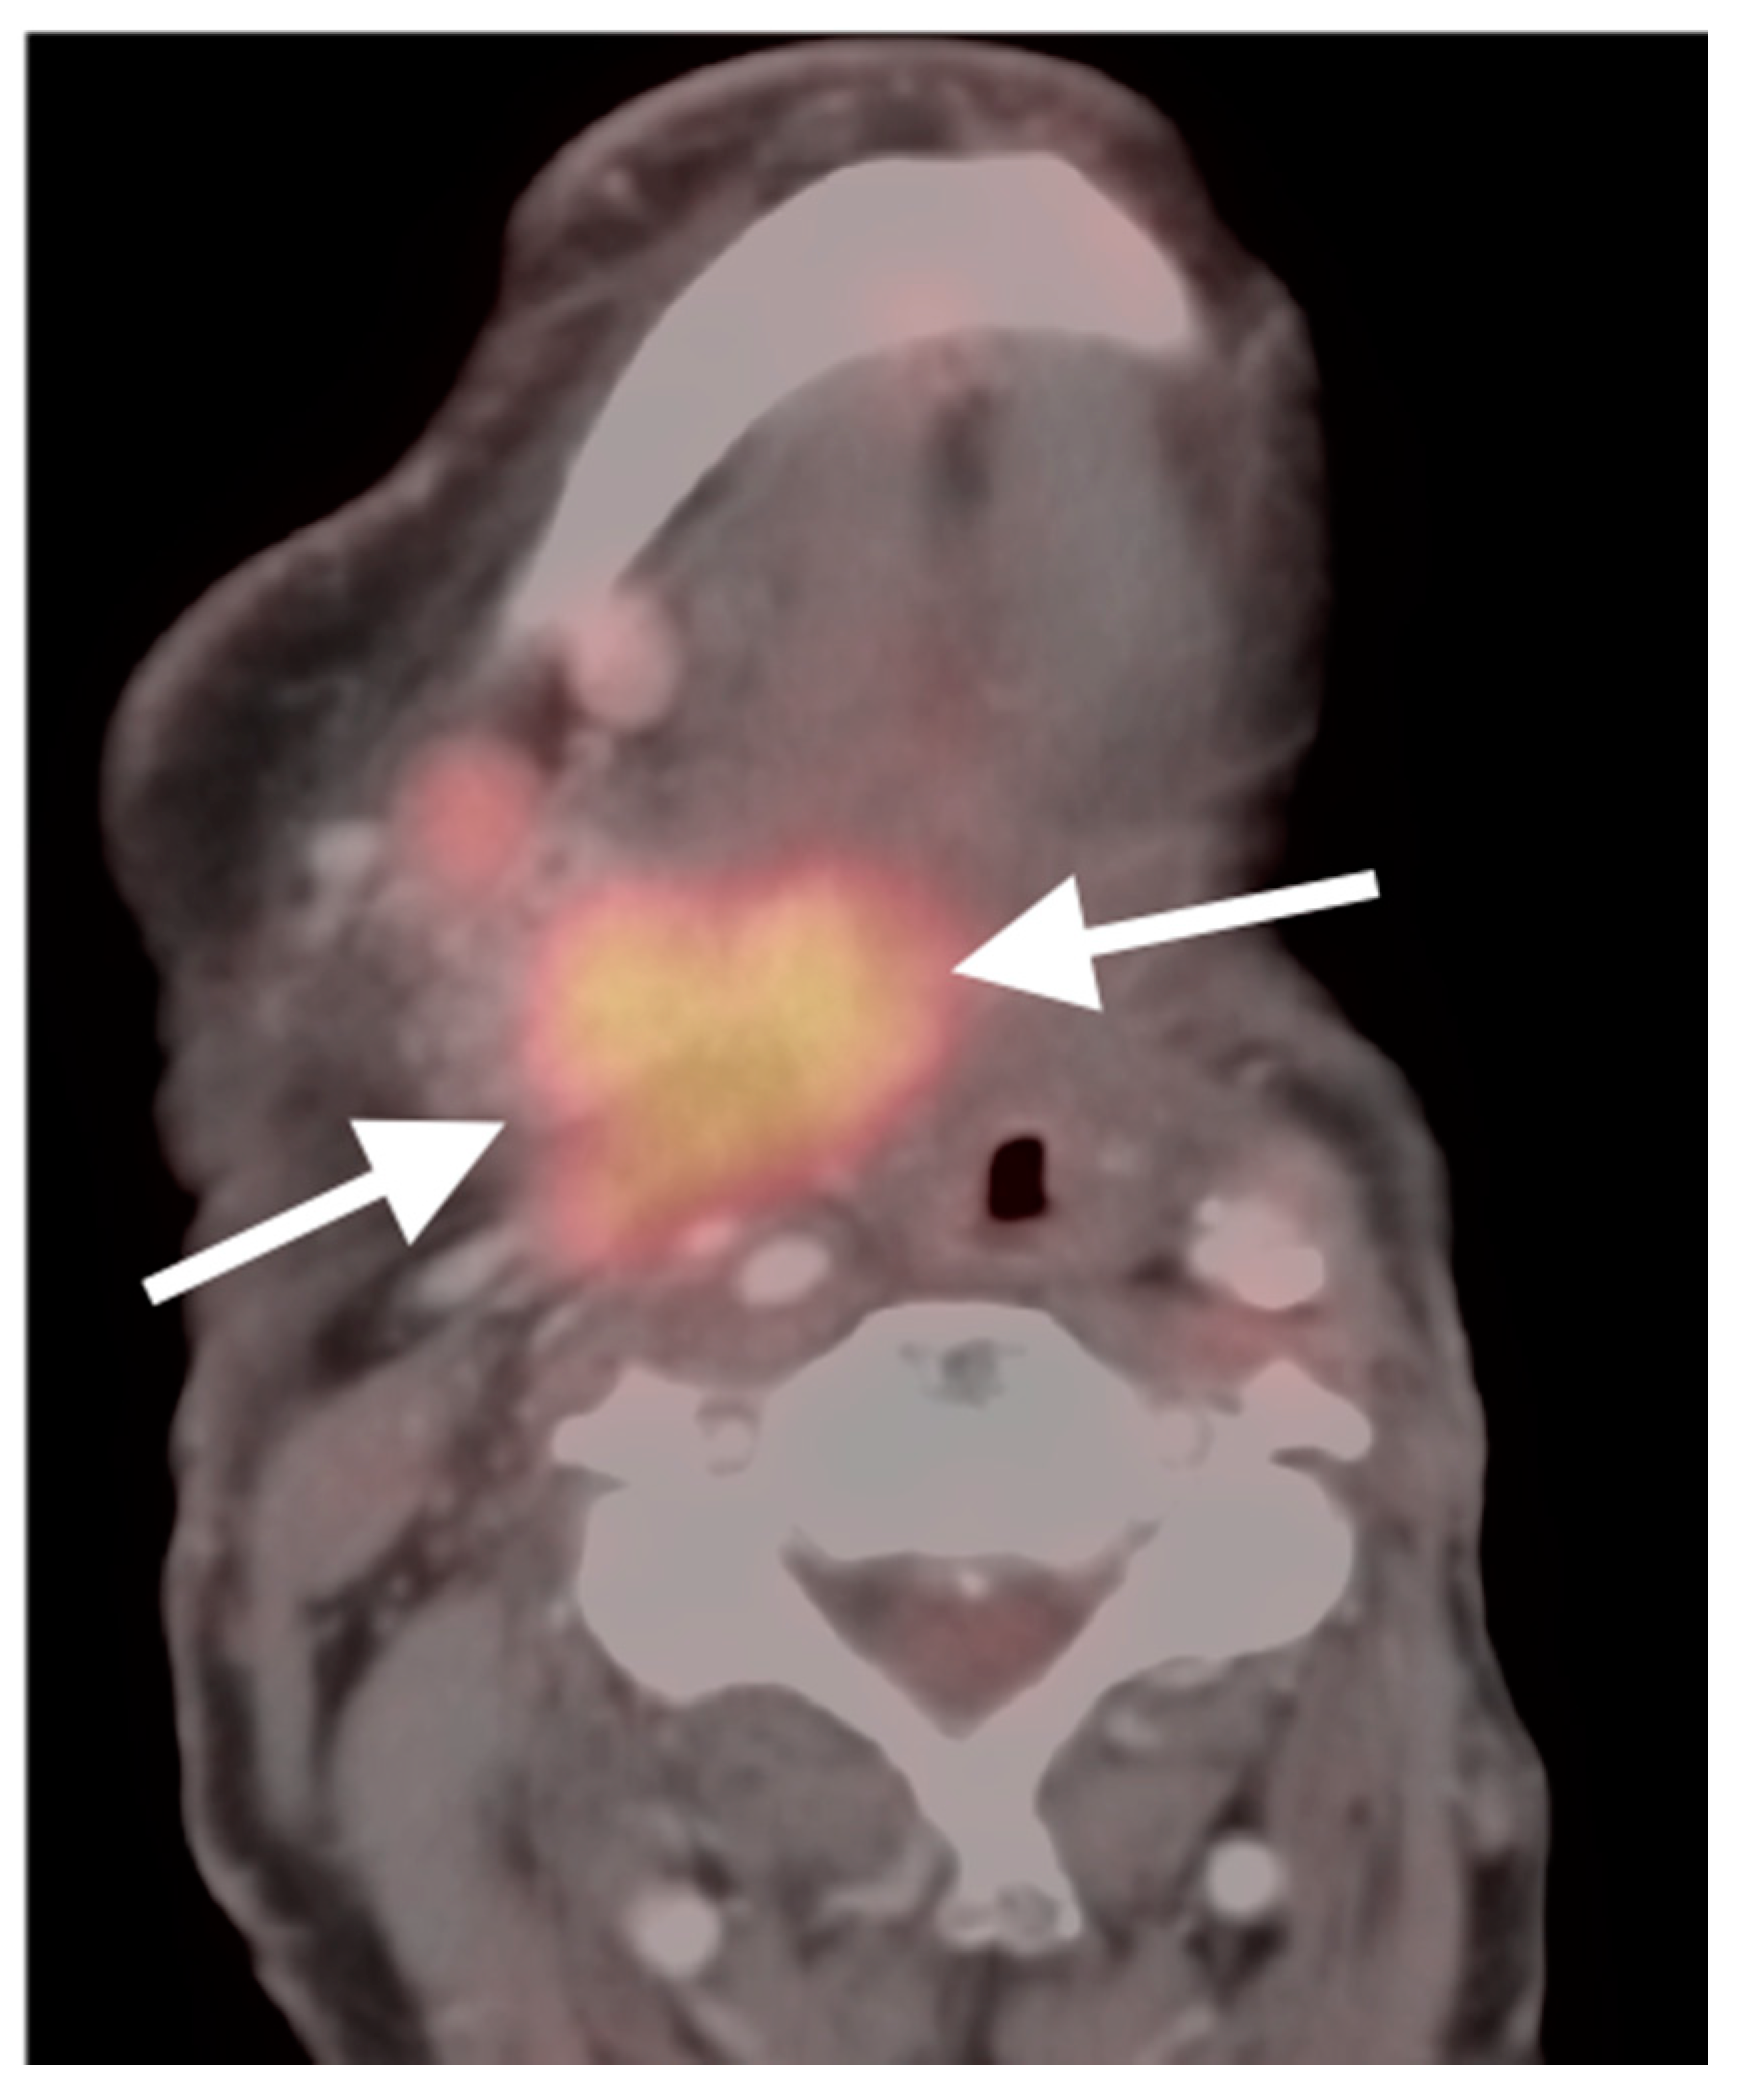

2.6. Thyroid Cancer

- Anaplastic thyroid cancer